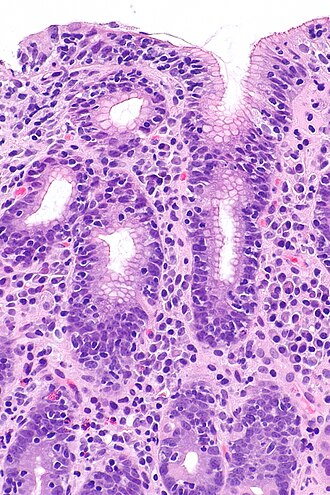

Lymphocytic gastritis. H&E stain. (WC/Nephron)

LM intraepithelial lymphocytes (>25 lymphocytes/100 epithelial cells)

Lymphocytic gastritis, abbreviated LG, is a rare form of gastritis, typically associated with celiac disease or Helicobacter pylori infection.

Features:[2]

• 25 lymphocytes / 100 epithelial cells.